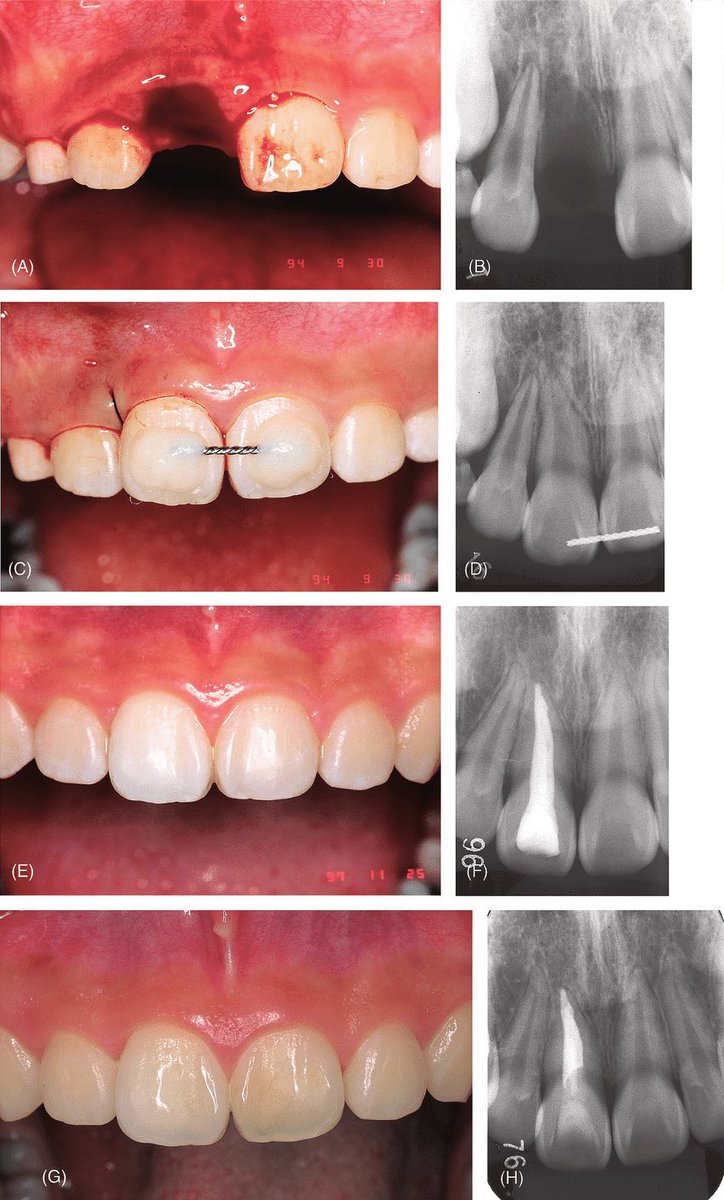

في حال حصل معاك او مع قريب لك او صديق وفقد سن دايم (السن اللبني لا يتم ارجاعه) بسبب الاصابه هنا خطوات تساعدك على الحفاظ على السن بعد سقوطه باذن الله:

إذا سقط أحد الأسنان بسبب الإصابة، فمن المهم التصرف بسرعة للحفاظ على السن وزيادة فرص إعادة الزرع بنجاح. فيما يلي تعليمات خطوة بخطوة حول كيفية الحفاظ على السن بعد سقوطه:

تذكر أن فرص نجاح إعادة زرع السن تقل مع كل دقيقة يخرج فيها السن من التجويف، لذلك من المهم التصرف بسرعة واتباع هذه الخطوات